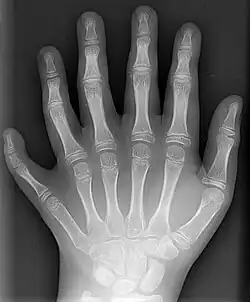

Röntgenaufnahme der linken Hand eines 10-Jährigen mit sechs Fingern (Hexadaktylie)

Röntgenstrahlung ist ionisierend. Sie kann dadurch Veränderungen im lebenden Organismus hervorrufen und Schäden bis hin zu Krebs verursachen. Deshalb ist beim Umgang mit der Strahlung der Strahlenschutz zu beachten. In der Frühzeit der Radiologie waren diese Effekte zunächst noch nicht bekannt, so dass mehrere Ärzte und Forscher erkrankten bzw. verstarben. Die Missachtung dieser Tatsache führte aber auch später, zum Beispiel bei Militärangehörigen, die in den 1950er bis zu den 1980er Jahren an mangelhaft abgeschirmten Radargeräten Dienst taten, zu Gesundheitsschäden, da die Geräte als Nebenprodukt auch Röntgenstrahlung abgaben (siehe dazu: Gesundheitsschäden durch militärische Radaranlagen). Es gibt eine entsprechende Stellungnahme des Ärztlichen Sachverständigenbeirats „Berufskrankheiten“ beim deutschen Bundesministerium für Arbeit und Soziales.[12]

Mit Röntgenstrahlung kann der menschliche Körper durchleuchtet werden, wobei vor allem Knochen, aber bei modernen Geräten auch innere Organe sichtbar werden (siehe auch Röntgen). Dabei wird ausgenutzt, dass das in den Knochen vorkommende Element Calcium mit Z = 20 eine deutlich höhere Ordnungszahl hat als die Elemente, aus denen die weichen Gewebe hauptsächlich bestehen, nämlich Wasserstoff (Z = 1), Kohlenstoff (Z = 6), Stickstoff (Z = 7) und Sauerstoff (Z = 8). Zudem werden Röntgenkontrastmittel eingesetzt, die meist Iod (Z = 53) oder Barium (Z = 56) enthalten. Neben herkömmlichen Geräten, die eine zweidimensionale Projektion produzieren, werden auch Computertomographen eingesetzt, die eine räumliche Rekonstruktion des Körperinneren ermöglichen.